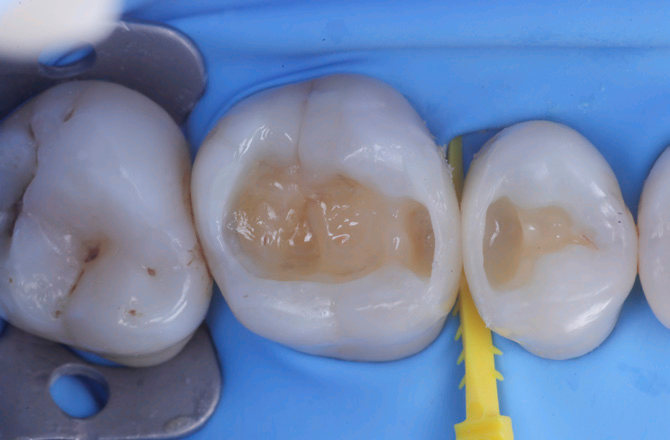

Fig.3 Aspetto vestibolare della cavità ultimateFig.4  Aspetto della chiusura cervicale e sulle pareti assiali dato dalla prima matrice

5

6

Fig.5 Aspetto della chiusura cervicale e sulle pareti assiali della seconda matriceFig.6 Aspetto occlusale delle pareti interprossimali appena create